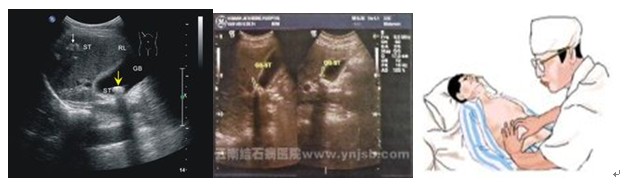

变体位常常能使疼痛加重,因此病人多喜欢向右侧静卧,以减轻腹疼。有些病人会有恶心和呕吐,但呕吐一般并不剧烈。大多数病人还伴有发热,体温通常在38.0℃~38.5℃之间,高热和寒战并不多见。少数病人还有眼白和皮肤轻度发黄。当医生检查病人的腹部时,可以发现右上腹部有压痛,并有腹肌紧张,大约在1/3的病人中还能摸到肿大的胆囊。化验病人的血液,会发现多数人血中的白细胞计数及中性白细胞增多。B超检查可发现胆囊肿大、囊壁增厚,并可见结石堵在胆囊的颈部。根据以上的症状、体格检查和各种辅助检查,医生一般能及时作出急性胆囊炎的诊断。

胆囊造影和B型超声肝胆扫描是诊断慢性胆囊炎很有价值的检查方法。胆囊造影可以发现胆结石、胆囊缩小变形,以及浓缩和收缩不良等情况,有时胆囊不显影。

B超检查除了可探查出胆结石和胆囊外型改变以外,还能看到胆囊壁有变毛糙、增厚等征象。有上述症状的病人,应及时就医,通过以上检查,一般可以明确慢性胆囊炎的诊断。

B超检查

3.血白细胞数和中性粒细胞比例增高,核左移或见中毒颗粒。4.B 超是诊断的主要依据,可显示胆囊肿大程度、积液、积脓、胆囊周围渗出性改变。

诊断检查 B型超声检查见胆囊体积增大,胆囊壁增厚,多数胆囊内有积液和胆石光团影。化验检查示自细胞计数升高伴核左移。